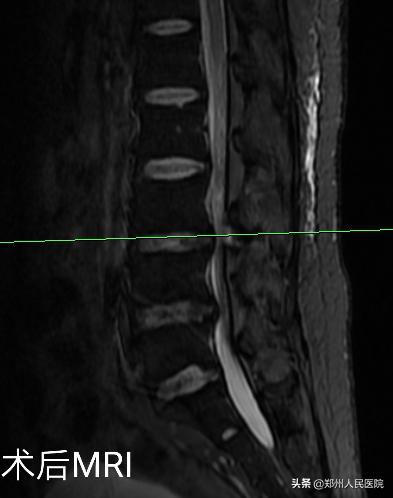

经过充分准备,对小葛实施的“单侧双通道UBE脊柱内镜术”如期举行。手术进行的十分顺利,经过一个半小时,手术成功。

在度过神经水肿期后,小葛的疼痛便消失了大半,由于手术对骨质的破坏很小,脊柱的稳定性得以最大程度的保留,手术后3天小葛就可以在腰部支具的辅助固定下行走活动,往日开朗的笑容又重新回到他的脸上。

为刘叔进行的“单侧双通道UBE脊柱内镜术”在不足两个小时后顺利结束,术中麻醉效果极佳,出血量只有数十毫升,清晰放大的视野下,突出的髓核及增厚的黄韧带完全摘除,骨性狭窄磨钻安全扩大减压,偶尔出现的小出血点也在射频刀头的控制下立即止血,轻松漂浮的神经根又重新出现了。

手术后,田明波主任问刘叔手术前后的感受,他只说了一句话,“要知道这个微创手术效果这么好,真是该早点来手术”。